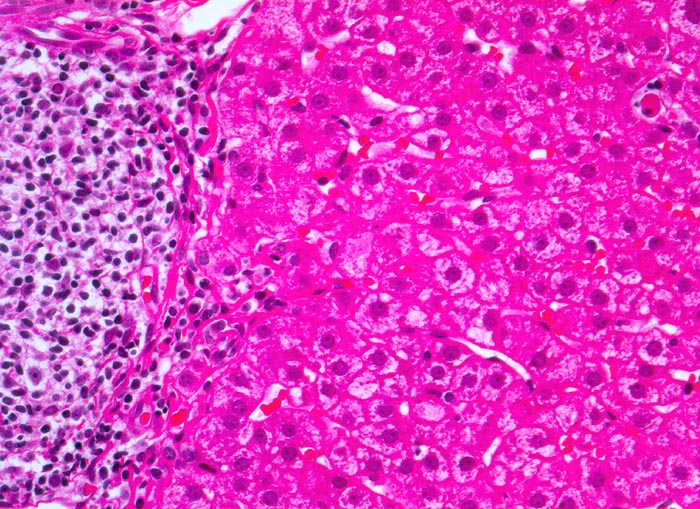

PathoPic – image database / PathoPic ID 4962 - chronische Hepatitis C mit geringgradiger Aktivität

chronische Hepatitis C mit geringgradiger Aktivität

Links im Bild Portalfeld mit starker Vermehrung von mononukleären Zellen. Das Infiltrat greift stellenweise auf das angrenzende Parenchym über (=periportale Hepatitis oder Interface Hepatitis). Das Parenchym ist weitgehend Entzündungsfrei. Es ist eine einzelne Apoptose erkennbar (=Councilman Körperchen oder Einzelzellnekrose).

Fibrose der Portalfelder mit portoportaler Septenbildung.

Das Übergreifen der Entzündung von den Portalfeldern auf das angrenzende Parenchym wurde früher als Piece Meal Nekrose bezeichnet und heute als Interface Hepatitis oder periportale Hepatitis.